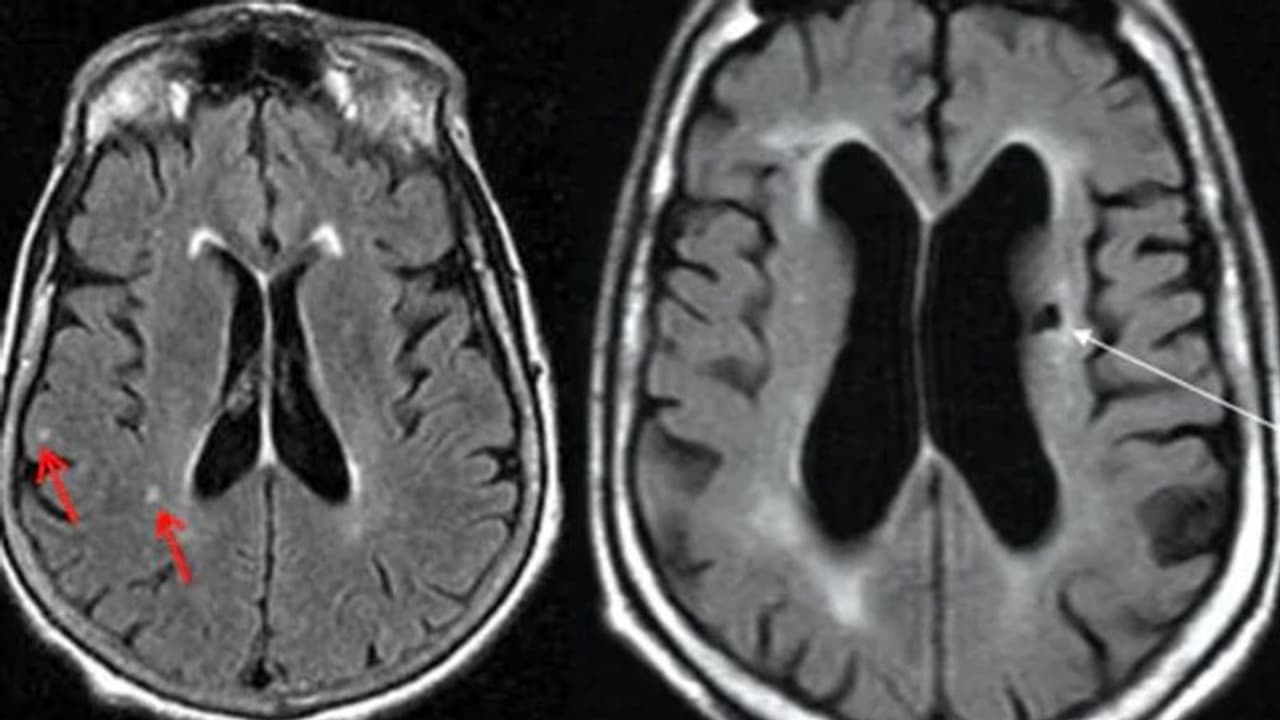

ഇത്തരത്തില് 'സൈലന്റ് സ്ട്രോക്കി'ന്റെ പല ലക്ഷണങ്ങളും മറ്റ് പല അസുഖങ്ങളുടേയും ലക്ഷണങ്ങള്ക്ക് സമാനമാണ്. അതിനാല് തന്നെ ഈ പ്രശ്നങ്ങള് ശ്രദ്ധയില് പെടുന്ന പക്ഷം ഒരു ഡോക്ടറെ കണ്ട് ആവശ്യമായ പരിശോധനകള് നടത്തി, ഇക്കാര്യം ഉറപ്പുവരുത്തുകയാണ് ഉചിതം. തലച്ചോറിന്റെ സി.ടി സ്കാന്, എംആര്ഐ എന്നിവയിലൂടെ സ്ട്രോക്ക് സംഭവിച്ചിട്ടുണ്ടോയെന്ന് ഡോക്ടര്ക്ക് കൃത്യമായി നിര്ണയിക്കാന് കഴിയും. ആ രീതിയില് ശാസ്ത്രീയമായിത്തന്നെ ഇതില് വ്യക്തത വരുത്താം.